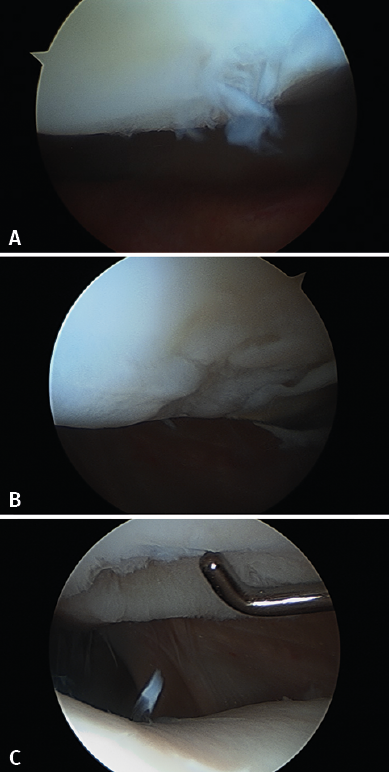

Figure 4. Arthroscopic views of the Outerbridge chondral lesion grades. A: grade I lesion; B: grade II lesion; C: grade III lesion.

Figure 4 shows arthroscopic images of lesions corresponding to grade II (Figure 4A), grade III (Figure 4B) and grade IV (Figure 4C).